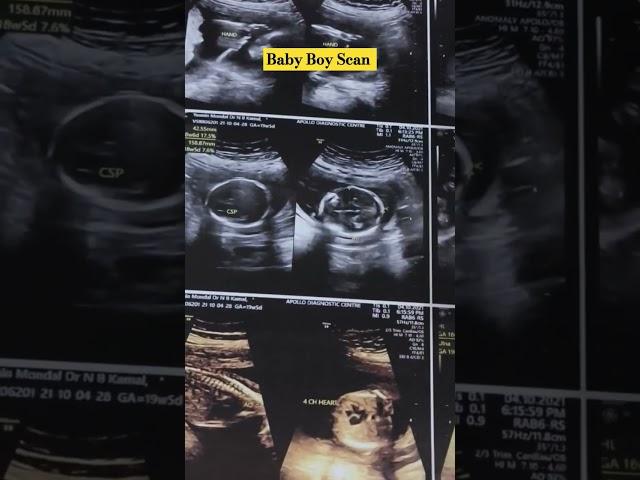

Showing Baby Boy in Ultrasound Report #babyboy #yasminlifestyle #anomalyscan #baby_boy_symptoms